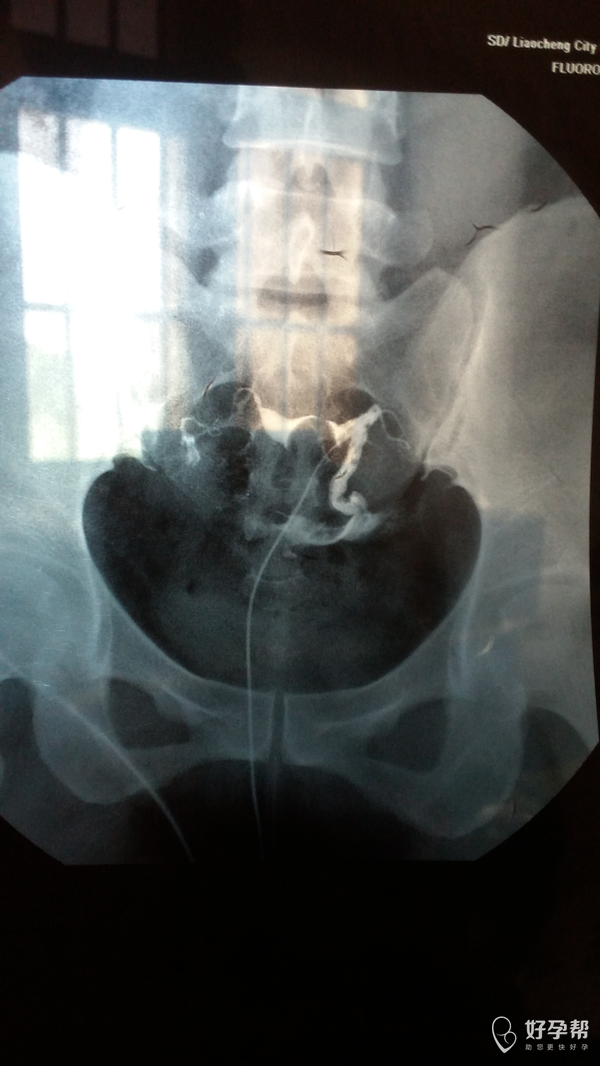

您好,双侧输卵管通畅的,但是双侧输卵管远端增粗,盆腔弥散不好,不排除盆腔粘连。